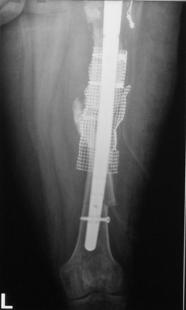

Trei din cele 38 de solduri investigate au prezentat ca indicatie operatorie fractura periprotetica, doua solduri fiind diagnosticate cu fractura Vancouver B3, iar unul cu fractura Vancouver B2. Fracturile Vancouver B3 au fost tratate in ambele cazuri prin extractia protezei si introducerea unei proteze tip DLS de 275 mm lungime impreuna cu solidarizarea ansamlului folosind cate o placa si 4 cabluri in fiecare caz. Fractura Vancouver B2 a fost tratata prin extractia protezei si inlocuirea acesteia cu o proteza tip Modular.